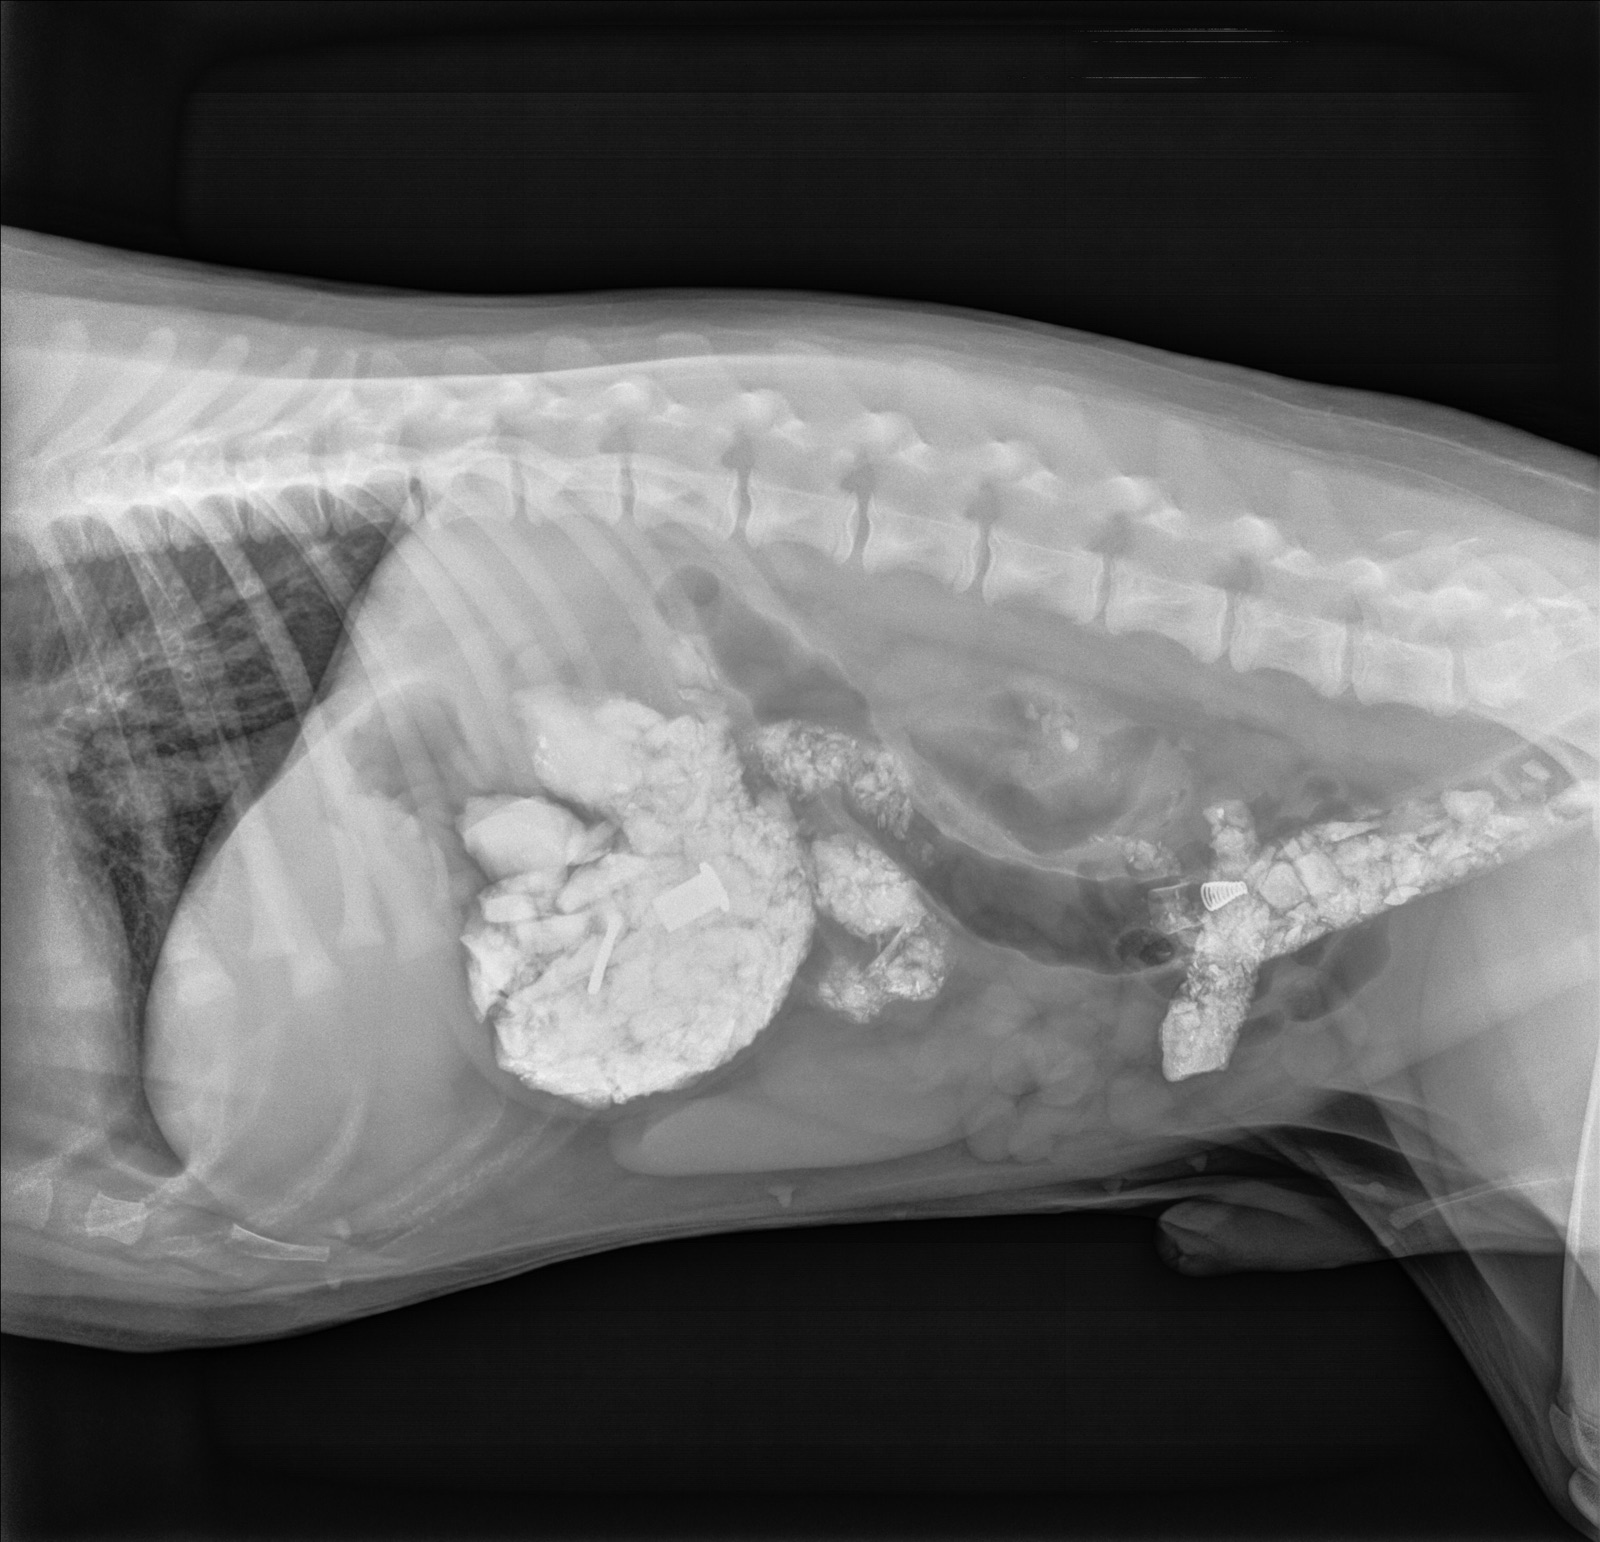

Scene #3: Problem Revealed

“Oh my, it seems you have eaten a collection of rocks!”

773BB21B-